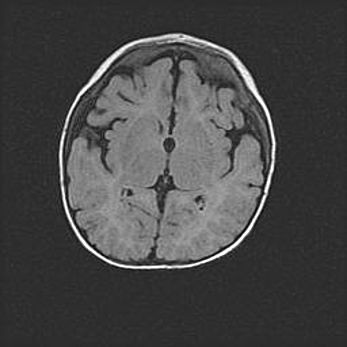

Лейкомаляция с кистозно-глиозной дегенерацией головного мозга.

Возраст: 2 месяца 25 дней

Вес: 6400 г

Окружность головы: 40 см

Срок гестации: 41 неделя

Лейкомаляцию относят к ишемически-гипоксическим повреждениям головного мозга, диагностируемым у новорожденных. При лейкомаляции в головном мозге обнаруживают очаги некроза, возникшие после тяжелой гипоксии и нарушения кровотока. В процессе морфогенеза очаги проходят три стадии: 1) развития некроза, 2) резорбции и 3) формирования глиозного рубца или кисты. Перивентрикулярная лейкомаляция (ПЛ) встречается примерно в 12% случаев среди новорожденных, обычно – у недоношенных детей, причем, частота ее зависит от массы, с которой младенец появился на свет. Наибольшее число малышей страдает лейкомаляцией, если масса при рождении 1500-2500 г.